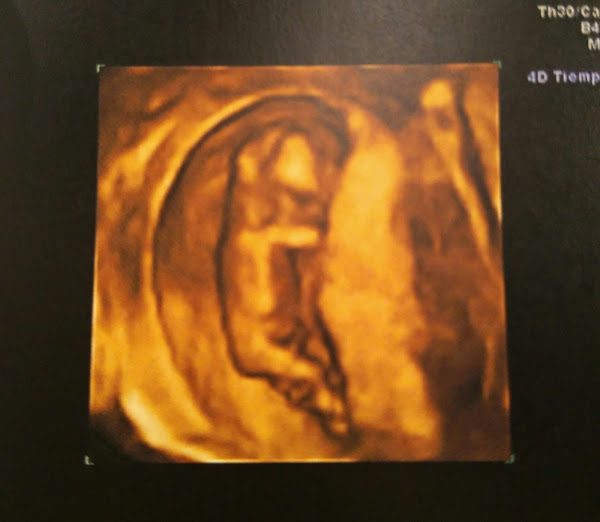

Y aquí está mi bolita!! Con una 4d y todo. Estoy eufórica, feliz, llena de amor y de mucha tranquilidad. Ayer estuve en la ecografía de las 12 semanas, en la que junto con la analítica ven el riesgo de síndromes como el Down, Edwars, etc. Fue toda una experiencia.

Según me echó el gel y puso el ecógrafo en mi tripa, ahí estaba, muy grande y muy formado desde la última vez. No había pasado ni 10 segundos y la doctora dijo que veía el pliege nucal muy bien. Empecé a llorar. Pensé en reprimirme y no comportarme como una primeriza sensiblona. Pero se me empezaron a caer las lágrimas y no pararon hasta el final. El Señor J también lloró y mi madre, creo que de verle a él.

La bolita no paró de moverse, estiraba las piernas y se tocaba la cara, no se lo puso fácil a la doctora, pero lo vio todo fenomenal.